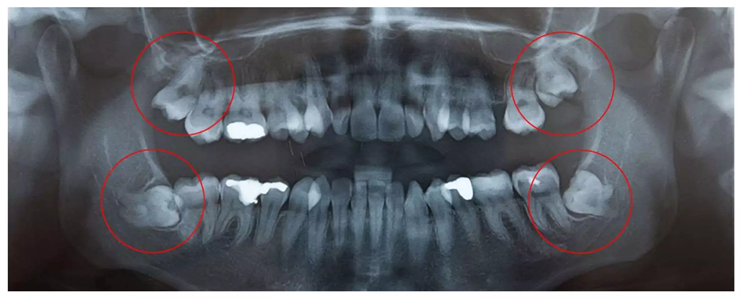

Radiographic Assessment:

Dental X-rays (like periapical or bitewing) help the dentist see bone loss around the teeth. Signs such as horizontal or vertical bone loss, widening of the space around the tooth root, and loss of bone lining show periodontitis (Jeffcoat, 1992; Hausmann, 2000).